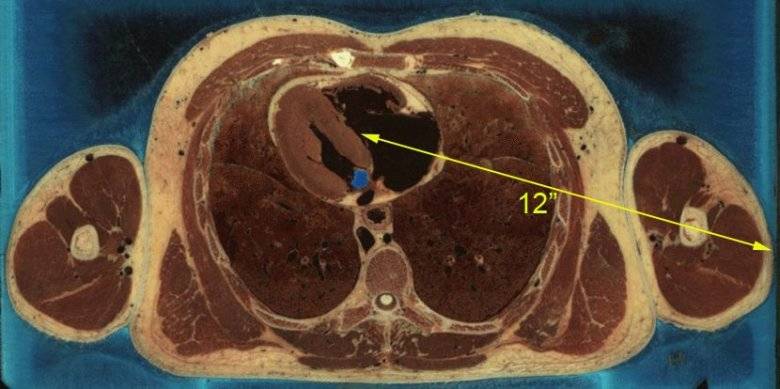

So I’ve actually taken this shot 7 times with 62 grain gold dots from a 10.5” AR. None of them “worked” as advertised, and the suspect’s arm was far more forward (closer to front of pectoral) which might actually help. Only 3 of the 7 made it into the close side lung. If it weren’t for the 8th shot (which didn’t have to get through the arm first), the suspect could have walked to the ER with some breathing difficulties after taking 7 rounds of highly rated bonded bullets from an AR at close range.

I’m familiar with another incident with almost identical shots with 77 grain (Hornady T2 if I recall). Same deal. In that case the suspect’s arm saved his life from multiple 5.56 rounds.